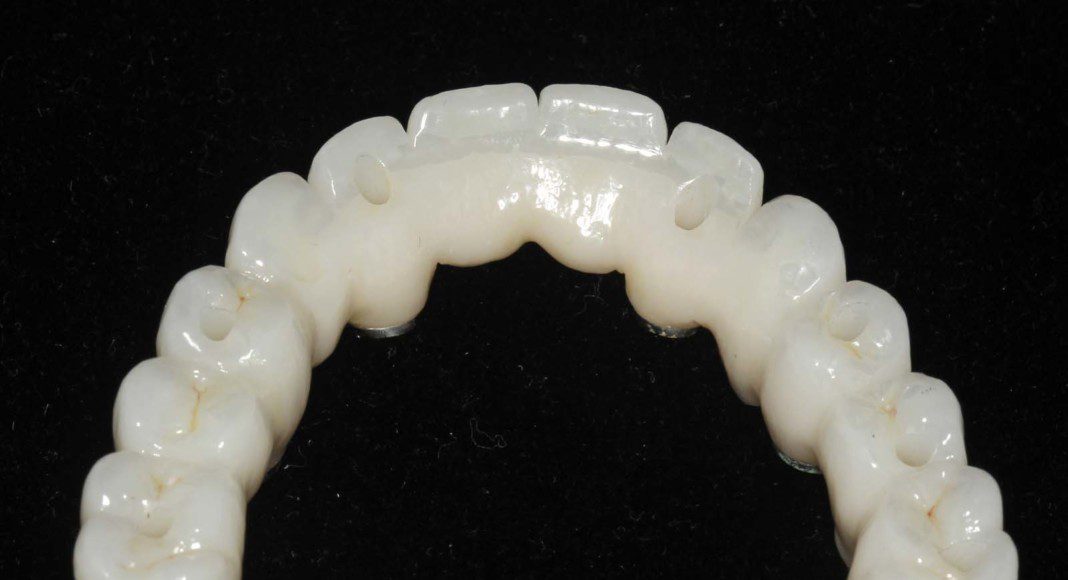

The intaglio (tissue side) of the upper, zirconia bridge. The contours are “convex” not concave for easy hygiene.

The intaglio (tissue side) of the lower, zirconia bridge. The contours are “convex” not concave for easy hygiene.

Occlusal view, upper, day of delivery. If you look closely, you can see the final prosthetic screw (blue). This channel is covered with composite resin.